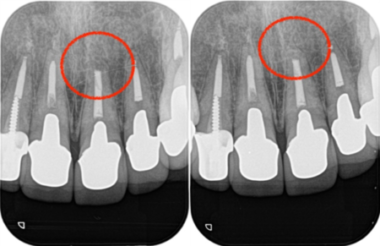

当院にて詳しく診査を行ったところ、左上1番の歯に根尖性歯周炎(虫歯や歯髄炎が進行し、歯の根の先周辺の歯周組織に炎症が生じた状態)が確認されました。

この炎症が、患者様が感じていた違和感の主な原因であると診断しました。

レントゲン画像がこちらになります。

術後およそ2週間で、患者様が訴えていた違和感は大きく改善されました。

その後も3ヶ月、1年と経過を追って確認した結果、現在に至るまで外科手術による瘢痕はほとんど見られず、

美しい歯茎のラインを維持したまま、無事に治療を完了することができました。

画像がこちらになります。